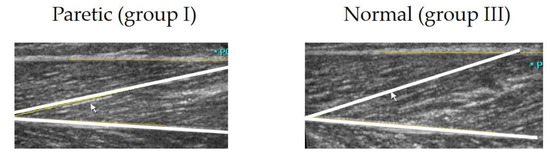

2.2. Procedure